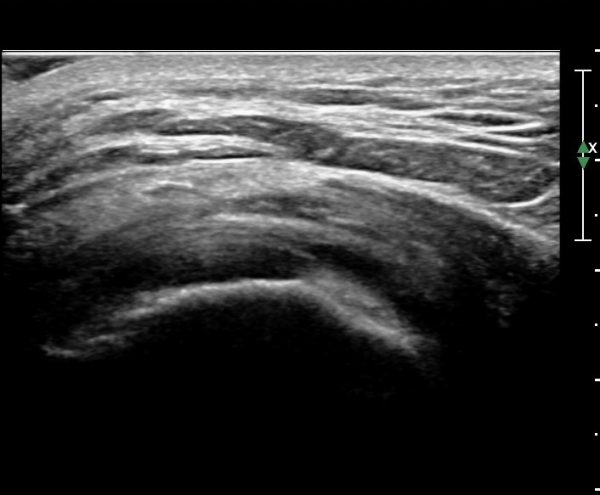

ŽÃËÀÚ¸¦ ¸Ó¸®ÂÊÀ¸·Î À̵¿ÇÏ´Ï ¼ö¾×Àú·ù°¡ ´õ ¸¹ÀÌ °üÂûµÈ´Ù(»çÁø 2, 3).